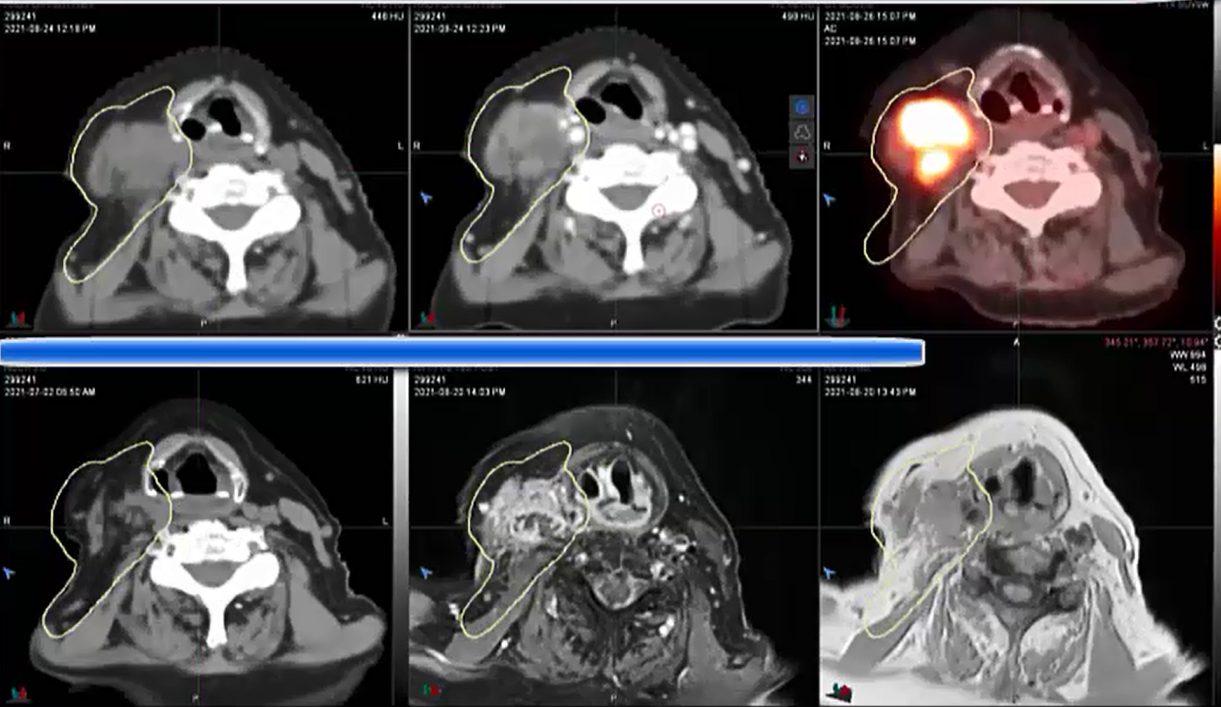

08/30/2021 - Dr. David Sher - Radiation Oncology - US Head & Neck

Base of Tongue, Unknown primary